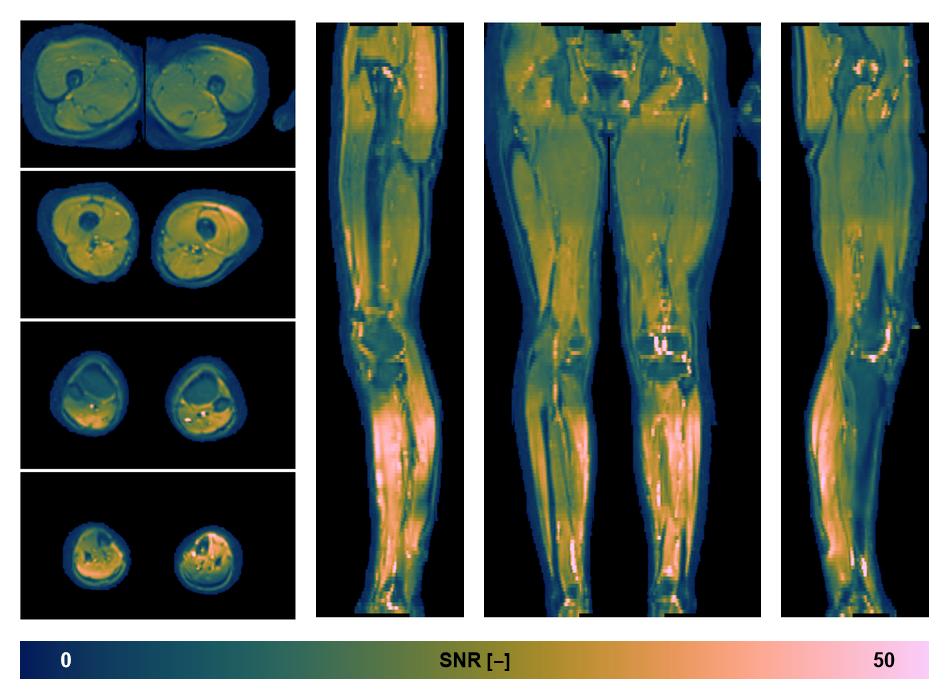

• SNR of the unweighted image

SNR distribution of the unweighted diffusion data.